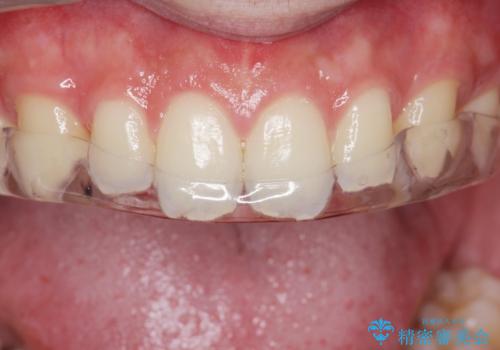

ナイトガードで歯の予防をしたい。

- 歯軋りが気になるとの事で来院。

歯が割れたりするのを予防したいとの事でしたのでナイトガードを作製しました。

ナイトガードを使用することにより歯が割れるリスクが低くなります。